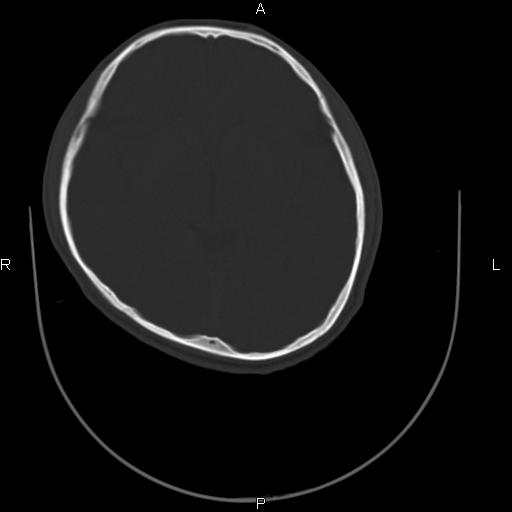

标题: CT27115:大家看一看,这孩子的颅骨表现? [打印本页]

标题: CT27115:大家看一看,这孩子的颅骨表现?

两名中学生打架,脑质内未见异常,未上传。

颅骨骨质未见异常。

颅骨未见骨折征象。

两例——颅骨结构正常,未见明显骨折征象。

感觉第2个颅缝密度高,额顶部板障有点厚,正常变异?地中海贫血?